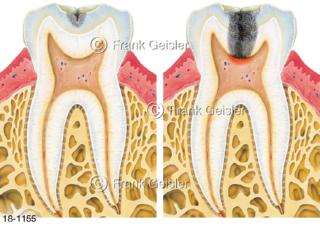

18-1155 Zahnerkrankung Zahnkaries Schmelzkaries Karies profunda durch Bakterien